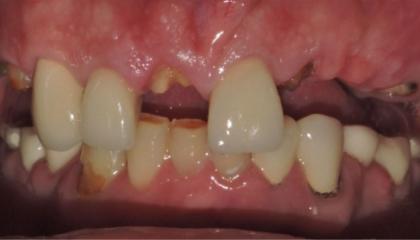

Before